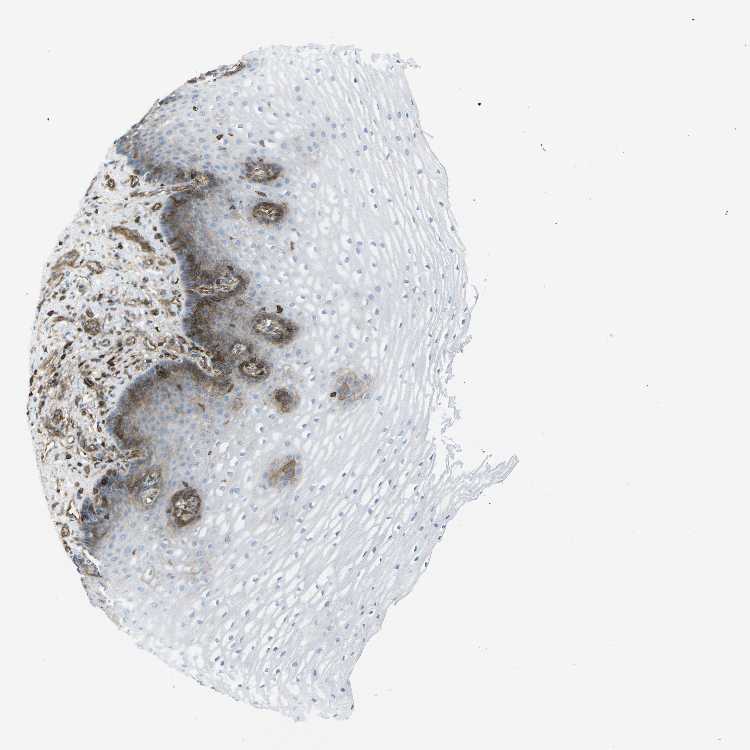

ESOPHAGUS - Antibody stainingi

Antibody staining in the annotated cell types in the current human tissue is reported as not detected, low, medium, or high, based on conventional immunohistochemistry profiling in selected tissues. This score is based on the combination of the staining intensity and fraction of stained cells.

Each image is clickable and will lead to virtual microscopy that enables deeper exploration of all samples and also displays staining intensity scores, fraction scores and subcellular localization as well as patient and tissue information for each sample.

Antibody CAB015418

Squamous epithelial cells Low